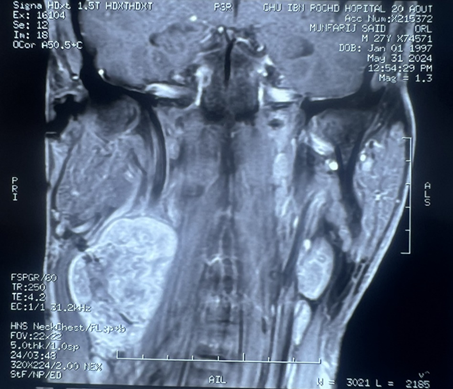

Magnetic resonance imaging (MRI)

of the neck confirmed a 39x38x60 mm properly limited mass with high signal

intensity on T1-weighted MRI and a heterogeneous, low signal intensity on T2

weighted MRI (Figure 1). After

intravenous administration of gadolinium-based contrast material, the lesion

showed irregular peripheral enhancement. Carotid artery angiography was

performed because of the close relationship between the mass and the carotid

artery. The angiography showed a normal filling in the right common, internal,

and external carotid arteries and their branches. (Figure 2).

Figure 2: Coronal (A) sagittal (B) and axial(C) view. Gray

arrow: well-circumscribed, h mass with dimensions of 39x38x60 mm in the right

lateral cervical region directly under the right sternocleidomastoid muscle,

separating the internal jugular vein and the carotid artery. Yellow arrow:

compressed internal jugular vein. Black arrow: carotid artery.